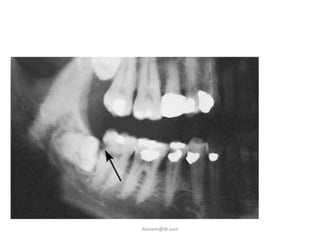

D. Root Resorption

• Impacted teeth cause

sufficient pressure on

the root of an adjacent

tooth to cause root

resorption.